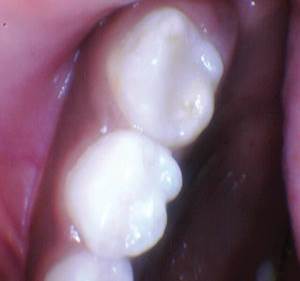

Figura 1 Vista preoperatoria del primer molar primario superior. |

Caso 1

Un paciente de 8 años presentó descomposición de OD en un primer molar primario con síntomas de pulpitis reversible. El diente fue el tratamiento planificado para una restauración de OD con Activa Bioactive Restorative (Pulpdent). Tras la excavación por descomposición, se produjo una exposición pulpar que requirió una pulpotomía terapéutica. Debido a la edad del paciente, me sentí cómodo con una pulpotomía terapéutica con Biodentine (Septodont) seguida de una restauración estética. Si el paciente hubiera tenido entre cuatro y cinco años, me habría restaurado con una corona de acero inoxidable debido a su historial comprobado de longevidad.